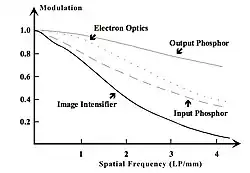

When the Fourier Transform of an LSF is calculated, then the imaging system’s response to sine waves of all spatial frequencies is obtained. This response is called the Modulation Transfer Function (MTF) - see Figure 6.9. It can be seen that the modulation falls off with increasing spatial frequency, as was seen with the Square Wave Response, but as a continuous curve representing all, and not just discrete, spatial frequencies.

The response of an ideal imaging system is also shown in the figure. Its constant value of 1.0 at all spatial frequencies implies that all details in the patient will be imaged perfectly, unlike our real intensifying screen whose modulation drops by 20% at spatial frequency, A, and by 90% at frequency, B, for example - whatever their absolute values might be.

Spatial frequency, B, in Figure 6.9 can be considered to be approaching the extreme of the resolving capability of an imaging system. The limiting spatial resolution is sometimes defined as the frequency where the modulation drops to 4%. When the resolving ability of two different image receptors is compared, as in Figure 6.10 for instance, we could infer from measuring the limiting resolution alone that system B was superior to system A, at 8 compared to 5 LP/mm. An MTF comparison would reveal however that system A in fact provides superior quality at frequencies less than about 3 LP/mm, which is where many features of clinical interest said to lie.

A major advantage of the MTF concept is that for an image receptor with a number of image transduction stages, the overall MTF can be obtained from the product of the individual component MTFs. This feature is demonstrated in Figure 6.12, which shows the component MTFs for an X-ray image intensifier. It can be seen that the contrast at high spatial frequencies is limited by the behaviour of the input phosphor and not the output phosphor in this hypothetical case. Thus, from a design point of view, a reduction in veiling glare in the input phosphor should improve the overall MTF of the XII. As an example of the multiplicative property of the MTFs, with reference to the figure, note that at a spatial frequency of 3 LP/mm the MTF of the image intensifier is: